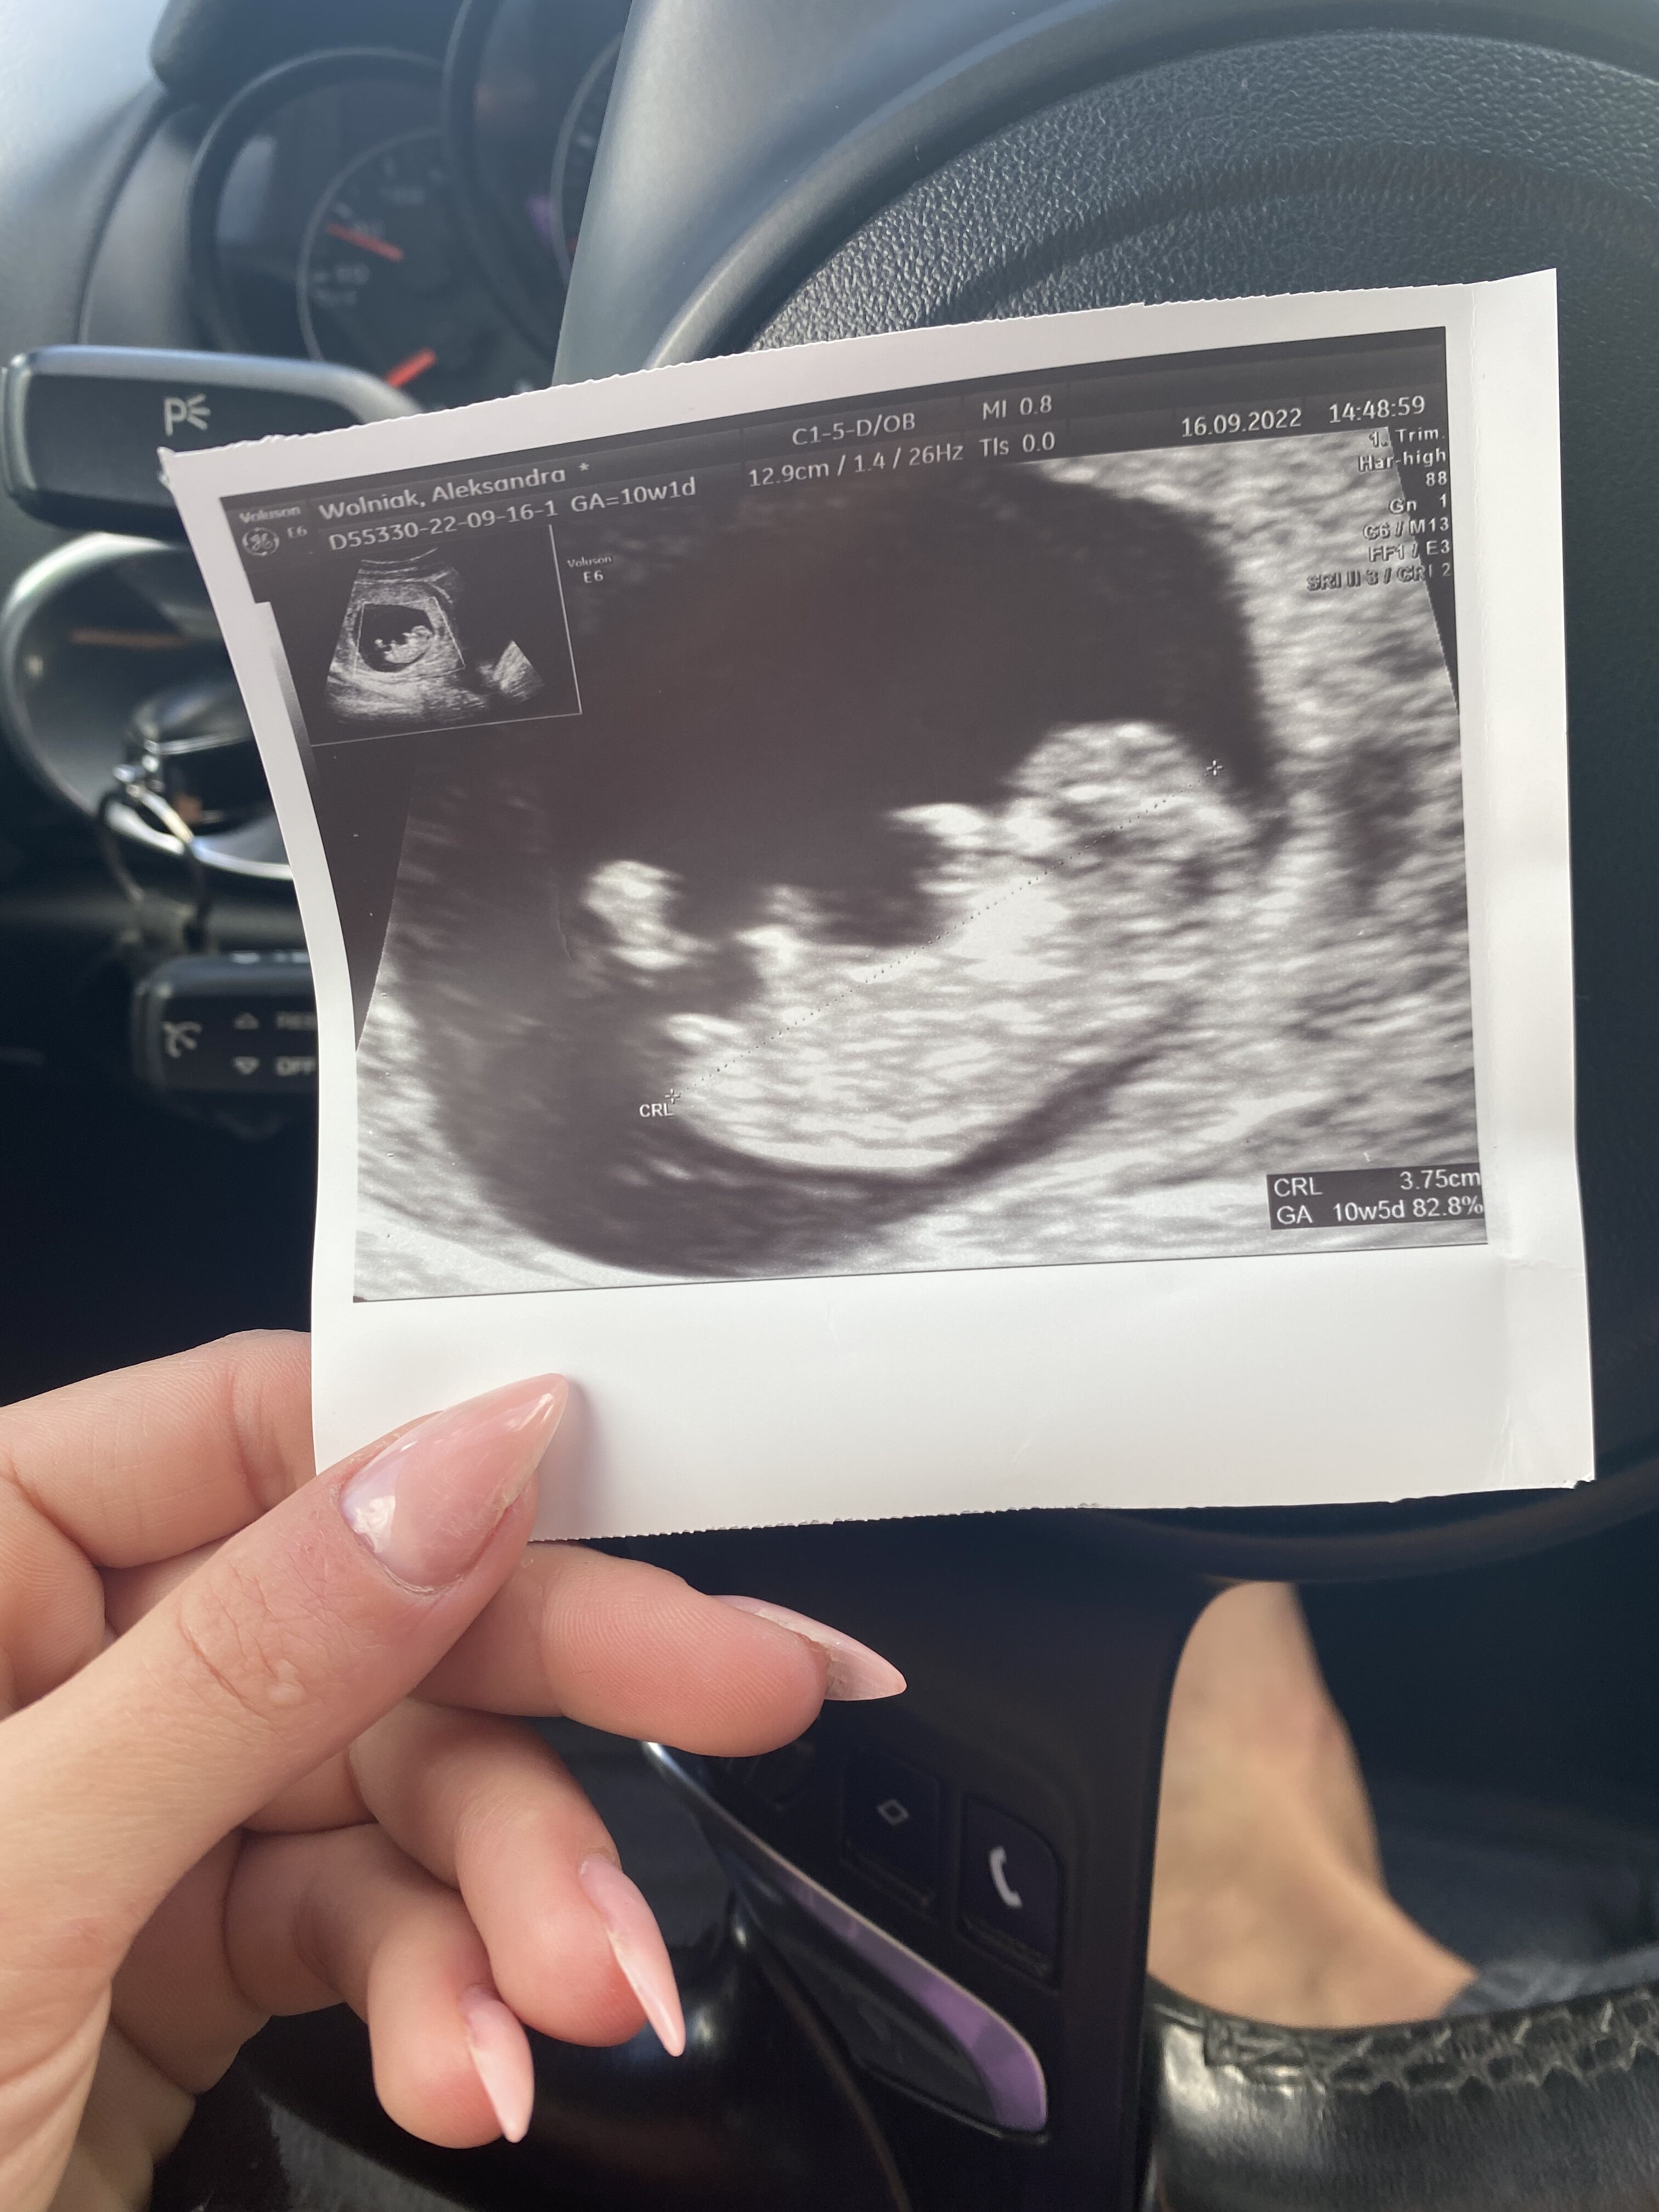

Co sądzicie? Lekarz mówi ze raczej chłopak a ja liczę na córcię bo chłopaka już mam :) i szczerze mówiąc ja siusiaka nie widzę.. A Wy? Teraz jestem w 20tc